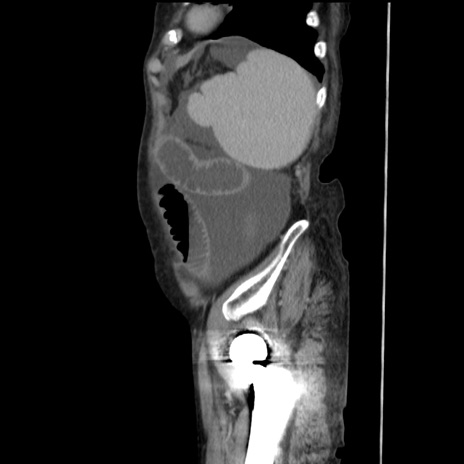

冠状断像

【症例】80歳代 女性

【主訴】腹部膨満感

【現病歴】他院にて肝硬変にてフォロー中。1週間前から便秘、腹部膨満感、臍部腫瘤あり受診となる。

【既往歴】肝硬変

【身体所見】腹部膨隆あり、皮膚変化なし、疼痛なし。

【データ】WBC 4600、CRP 0.25